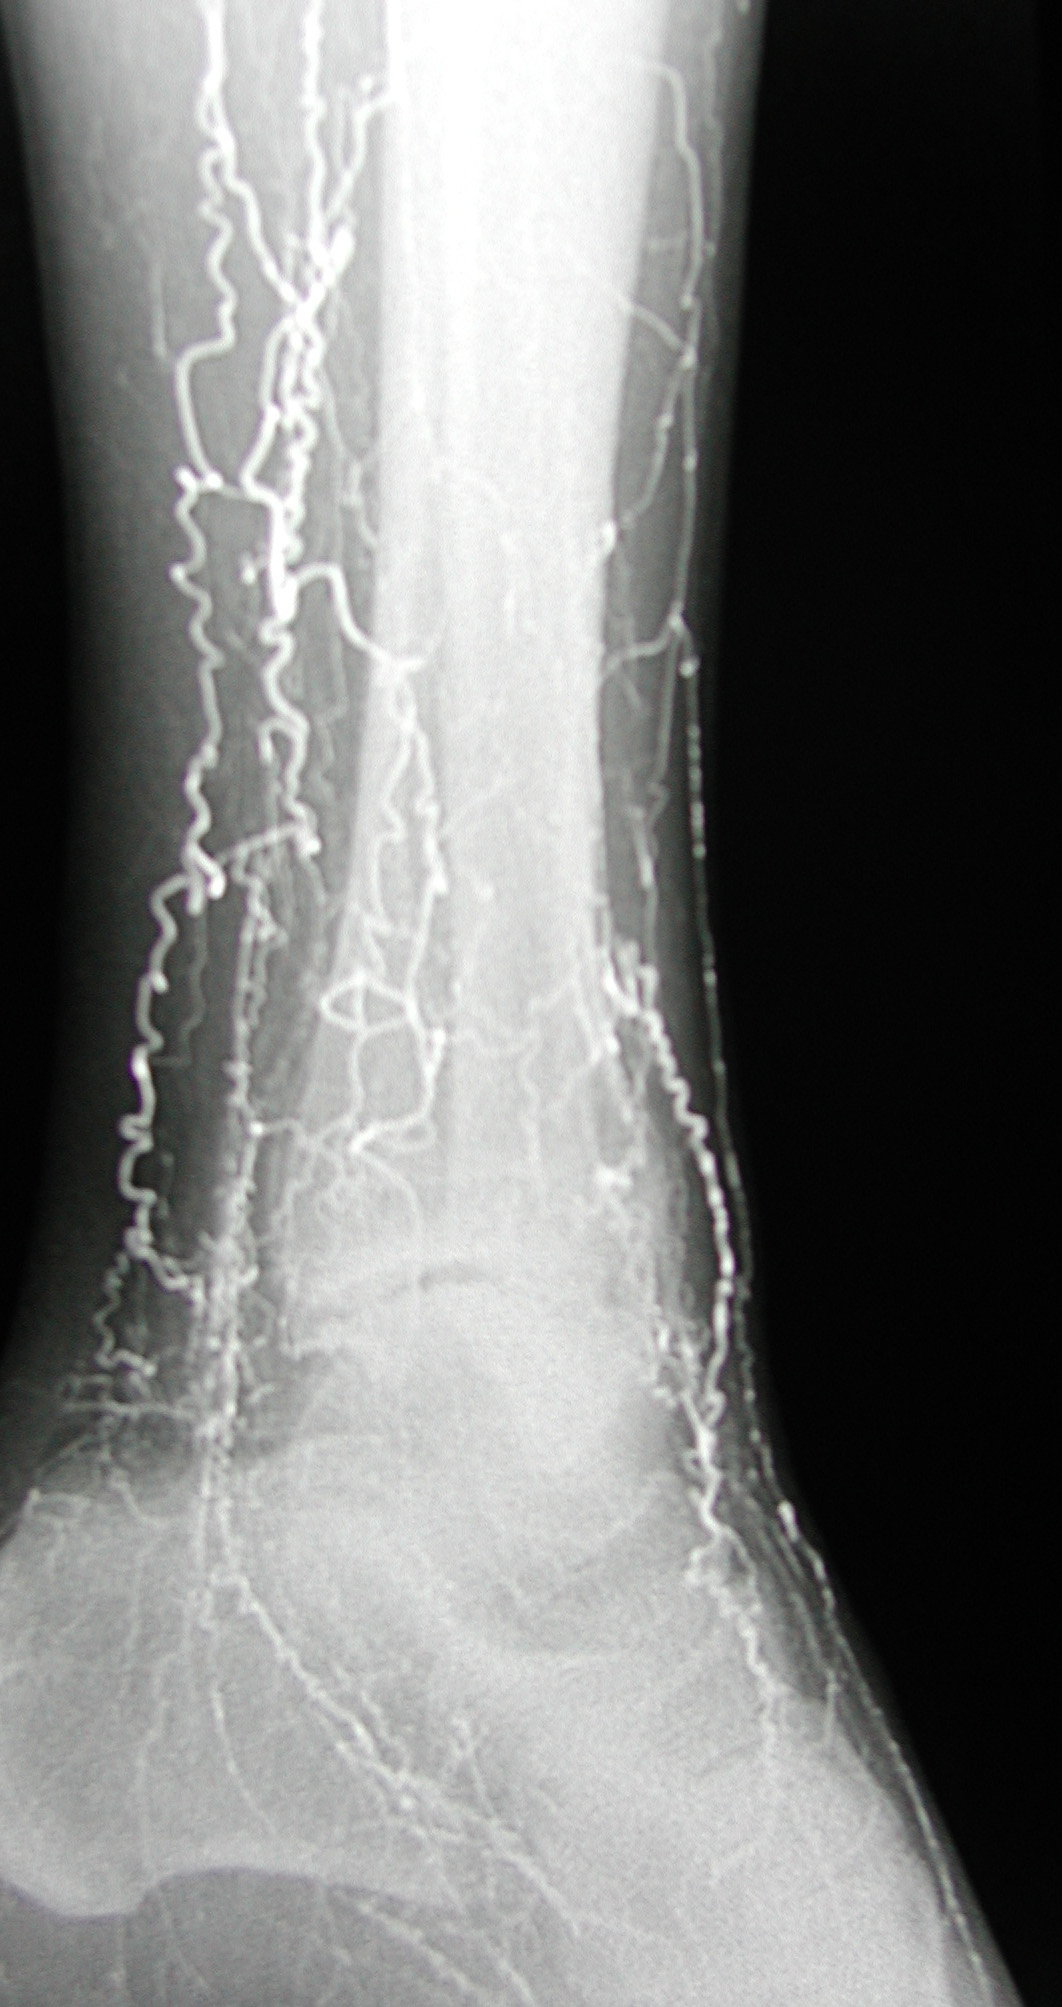

38 year old male with a history of smoking and no history of diabetes, hypertension, or hyperlipidemia who presents with cold and painful feet.